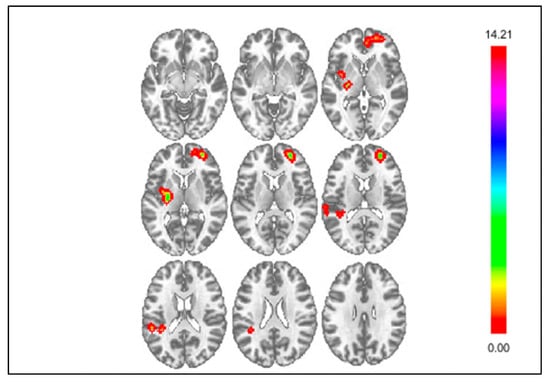

3.2. Results of Exploratory Connectivity Analyses

| Monetary Gain | ||||||

| DS Seed | Parietal Operculum Cortex | 51 | +51 | −21 | +24 | 4.5 |

| mPFC Seed | n.s. | --- | --- | --- | --- | --- |

| Insula Seed | vmPFC | 52 | −24 | +69 | −06 | 3.92 |

| Social Acceptance | ||||||

| DS Seed | n.s. | --- | --- | --- | --- | --- |

| mPFC Seed | Parietal Operculum Cortex | 283 | −51 | −36 | +15 | 4.63 |

| Insula Seed | DS | 53 | −03 | +03 | +06 | 4.88 |